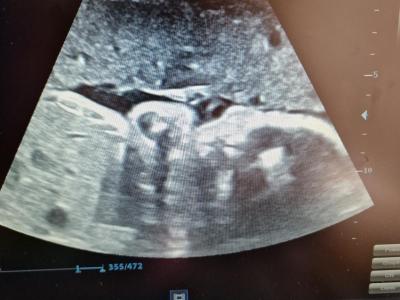

14. April 2025Von Herzen bedanken wir uns bei allen Förderern und Freunden, die es, auch Dank zusätzlicher Spenden, möglich gemacht haben. So kann die Schwangerschaftsvorsorge wieder wie gewohnt angeboten werden. Ebenso Herzecho und Doppler-Utraschall-Untersuchungen.

Die Bilder und das Dankesvideo, welche uns aus Kenia erreicht haben, teilen wir gerne mit euch.